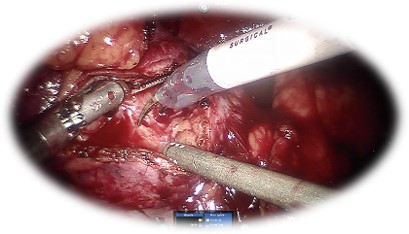

Prostatectomia radicală robotică:

• Rezultate oncologice superioare la 5 ani

• PSA nedetectabil în peste 90% din cazuri

(vs laparoscopic 75%, clasic 80%)1

• Cea mai bună rată de recuperare a continenței urinare postoperator

•  97% vs 80% în favoarea chirurgiei robotice

• Cea mai bună rată de prezervare a funcției erectile postoperator

• Prin prezervarea bandeletelor neurovasculare

• 41.9% vs 21.2% vs 16.7%    robotic vs laparoscopic vs classic